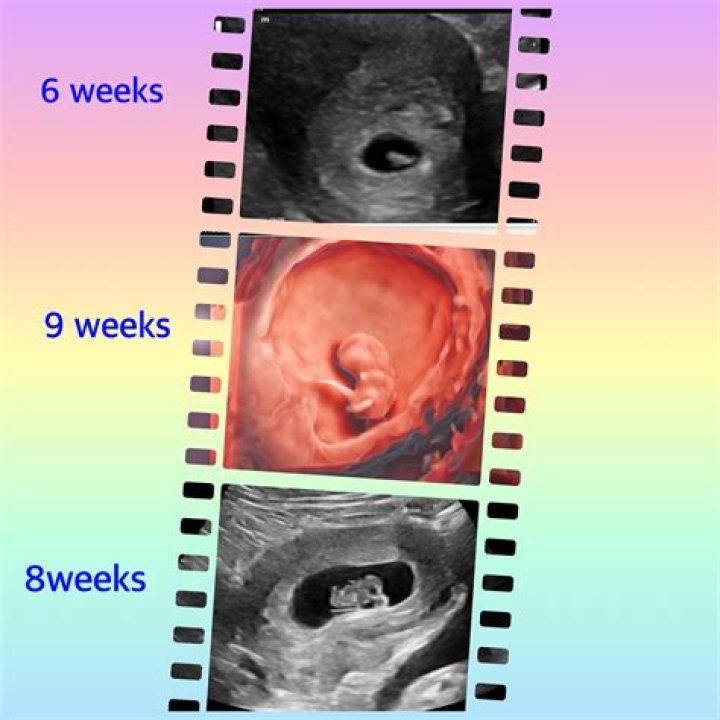

You can have an early pregnancy scan from just 7 weeks, but what you see on the screen might not look much like what you’re expecting. Your baby still has...